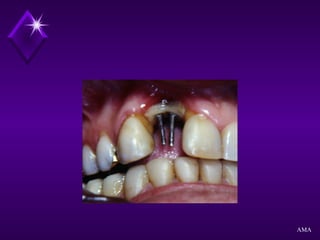

Objetivo inicialObjetivo inicial

Inválidos orais

Objetivo atualObjetivo atual

Reabilitação de áreas edentulas